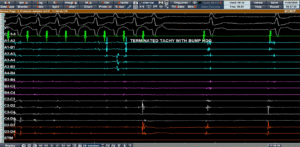

Induction and Entrainment: Confirming the Diagnosis

During the electrophysiology study (Page 4), tachycardia was induced using programmed stimulation.

Ventricular entrainment pacing demonstrated a VAAV response, confirming an atrial tachycardia/atrial flutter mechanism. The tachycardia cycle length (TCL) was approximately 310 ms.

Since atrial flutter typically represents a macro re-entrant circuit, mapping of both right atrium (RA) and left atrium (LA) was planned using a high-density grid catheter to create a Local Activation Time (LAT) map.

Interestingly, the HD grid catheter mechanically “bumped” the tachycardia, leading to termination.

Despite attempts, tachycardia could not be reinduced easily, further supporting a fragile re-entrant substrate dependent on a specific conduction channel.